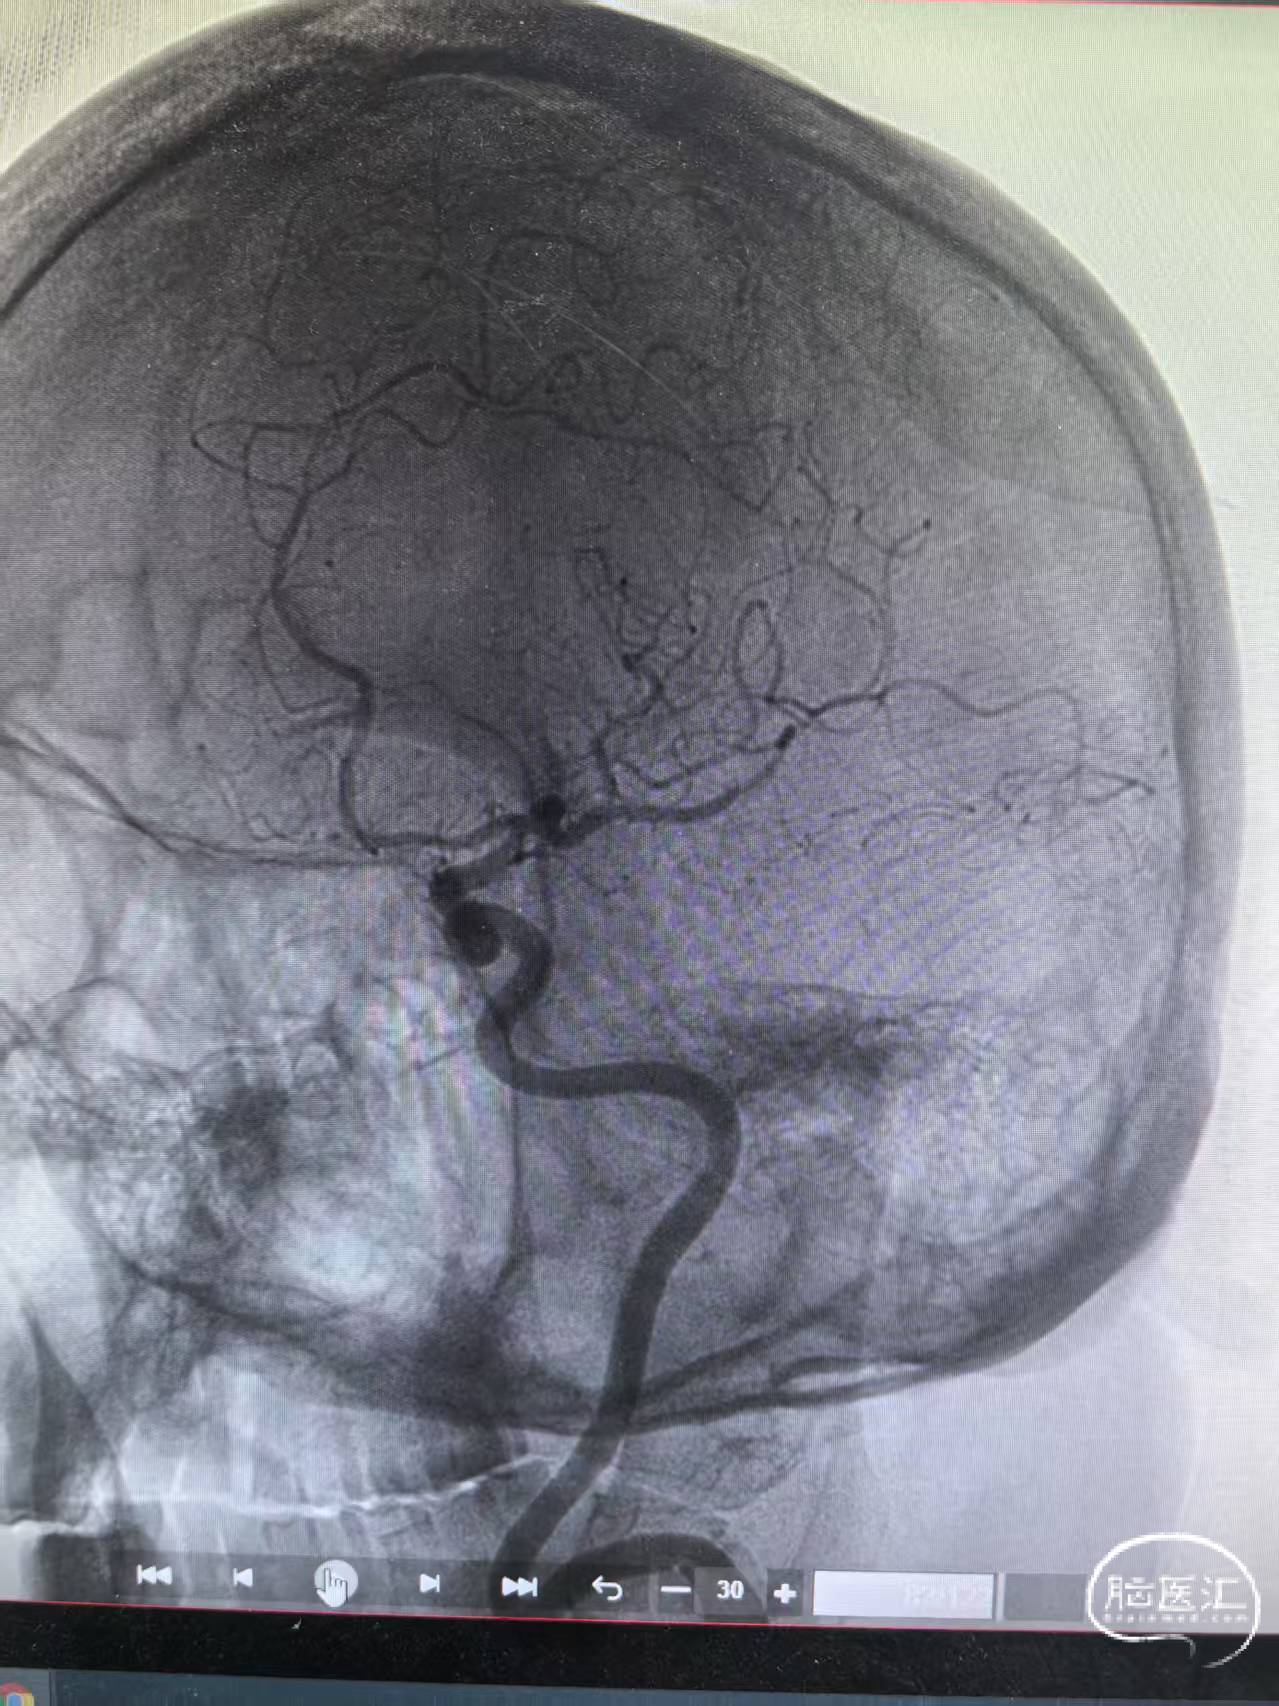

颈内动脉侧位造影三级再通

左侧颈内正位造影再通